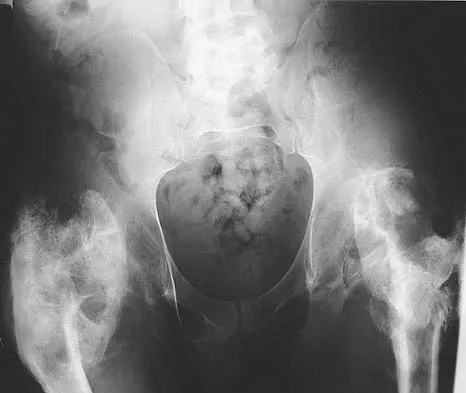

Question 1

A 16-year-old high school football player sustains an injury to the left hip. The avulsed fragment identified by the arrow in Figure 34 represents the origin of which of the following structures?

The avulsed fragment represents the origin of the rectus femoris from the anterior inferior iliac spine and the brim of the acetabulum. Avulsion of the anterior inferior iliac spine is much less common than avulsion of the anterior superior iliac spine with its origin of the sartorius. The origin of the gluteus minimus is from the outer cortex of the iliac wing and has not been reported as a source of bony avulsion. The hip capsule is composed of the ischiofemoral and pubofemoral ligaments, in addition to the iliofemoral ligament. The pelvic attachment of the ischiofemoral ligament is from the ischial part of the acetabulum posteriorly, while the pubofemoral ligament attaches to the pubic portion inferiorly. Technically, ligaments do not have origins and insertions as muscle tendon groups do, but have attachment sites. Metzmaker JN, Pappas AM: Avulsion fractures of the pelvis. Am J Sports Med 1985;13:349-358.